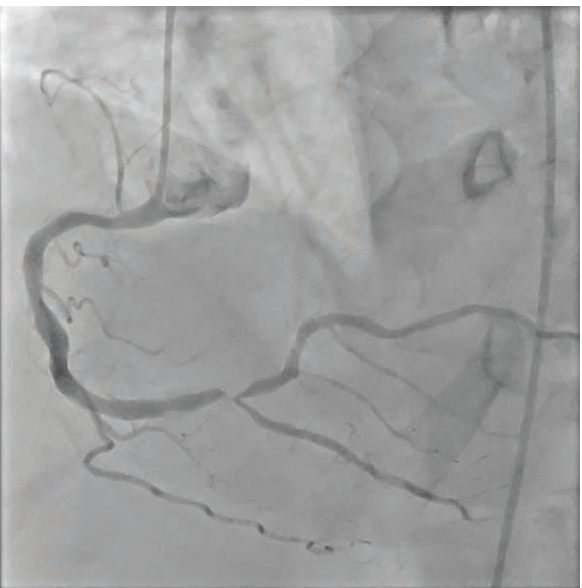

A balloon was inflated in the distal RCA, crushing the stent’s proximal portion. Following balloon inflation, a 4.0 mm x 23 mm drug-eluting stent was deployed in the distal RCA extending into the RPL branch, followed by a second inflation (Figure 2). Stent visualization (Artis icono floor CLEARstent technology from Siemens Healthineers) clearly articulated the stent borders (Figure 3). Proximal optimization of the distal RCA stent was performed with a 4.0 noncompliant (NC) balloon. The final angiogram showed good angiographic result, with thrombolysis in myocardial infarction (TIMI)-3 flow in all vessels (Figure 4).